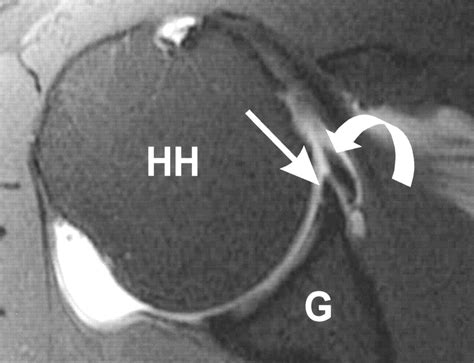

Diagnosing a Superior Labral Anterior Posterior tear can be complex because the symptoms often mimic other shoulder pathologies. Physical examinations usually involve orthopedic tests, such as the O’Brien test or the Biceps Load test, which are designed to put tension on the labrum and reproduce pain. Since clinical exams have limitations, radiologists often use Magnetic Resonance Imaging (MRI) with contrast—specifically an MRA—to visualize the tear clearly.

To grasp the severity of a Superior Labral Anterior Posterior tear, one must first visualize the shoulder anatomy. The glenoid (socket) is relatively shallow, which allows for a wide range of motion. The labrum deepens this socket, providing a stable cradle for the humerus (upper arm bone). The “superior” portion of this labrum serves as an anchor for the biceps tendon. When this area is subjected to excessive force, repetitive stress, or acute trauma, the tissue can fray, tear, or detach from the bone. The tear is described as “anterior to posterior” because it extends from the front (anterior) to the back (posterior) of this specific attachment point.